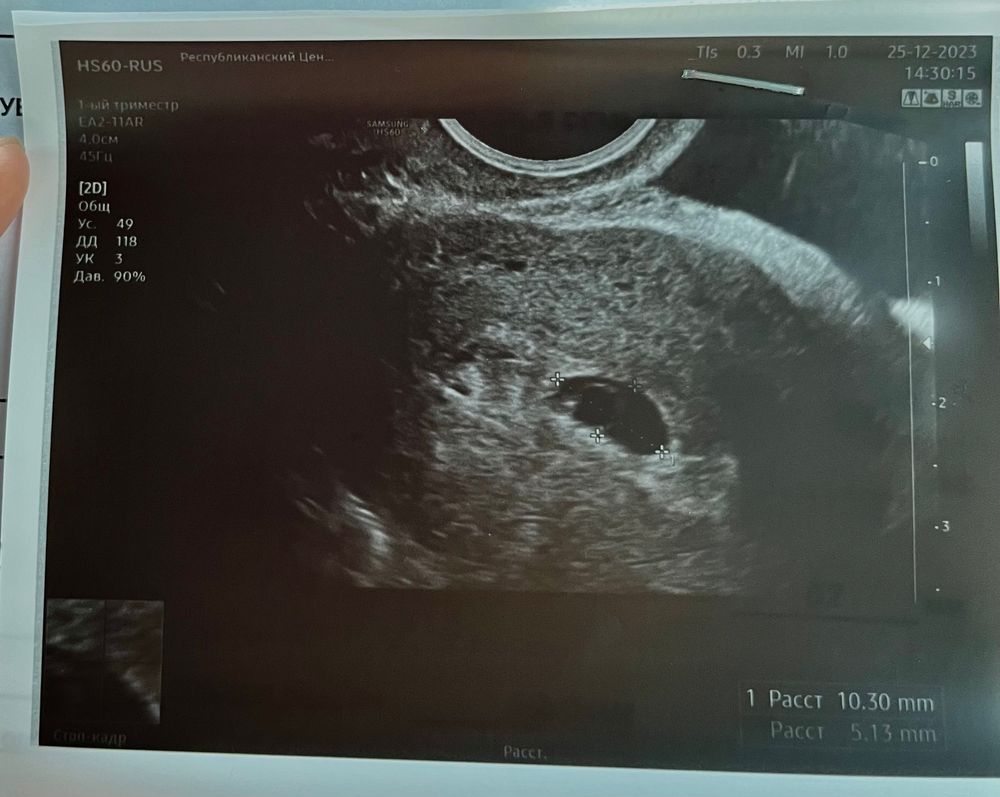

У вас ктр всего 1,5 мм, могли и не увидеть, сердечко должно появиться до 4-6 мм, сходите дней через 4-5, все будет понятно. Удачи вам)

Плодное яйцо очень маленькое даже для 6 недель,10*5 это средний внутренний диаметр 7,5 плохо выросло за неделю 2 мм это очень мало,у меня по 4 мм за неделю росло и это тоже плохо,замершая была,хгч плохо рос и странно что срок поставили 6 недель,у вас и пя и ктр на 5 недель,в 6 недель ктр 4-5 мм и пя от 15 мм и выше В 5 недель пя 3 мм В 6 недель пя 7 мм,жм 3,ктр 3 и сб + В 7 недель пя 12,жм 4,5,ктр 8 и сб + В 7,5 недель сб- замершая

Кристина, 10+5 и разделить на 2 получается свд пя,смотрят не длину ведь и не ширину,а средний внутренний диаметр,а он у вас 7,5 получается К примеру у меня 3 размера стояло 22,5*10*20 и свд 17,5,т.е пя 17,5,а не 22,5

Динамика тестов и хгч 4-12дпп Предновогоднее узи🙏🌸🌸🌸